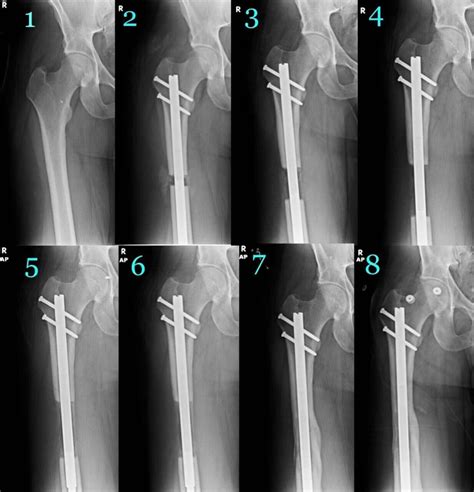

At its core, leg lengthening surgery, medically known as distraction osteogenesis, relies on the body’s innate ability to regenerate new bone and soft tissue. The process begins with an orthopedic surgeon making a precise cut in the bone, known as an osteotomy. Once the bone is divided, a specialized device, usually an internal intramedullary nail, is implanted into the marrow cavity.

After the initial surgery, a period called the "distraction phase" begins. During this time, the device is gradually lengthened—often via an external remote control—by a small amount each day, typically about one millimeter. This slow separation creates a gap where new bone tissue, nerves, and blood vessels slowly form to bridge the space. Following the distraction phase, the bone must undergo a consolidation phase, where the newly formed bone mineralizes and hardens to reach full strength.